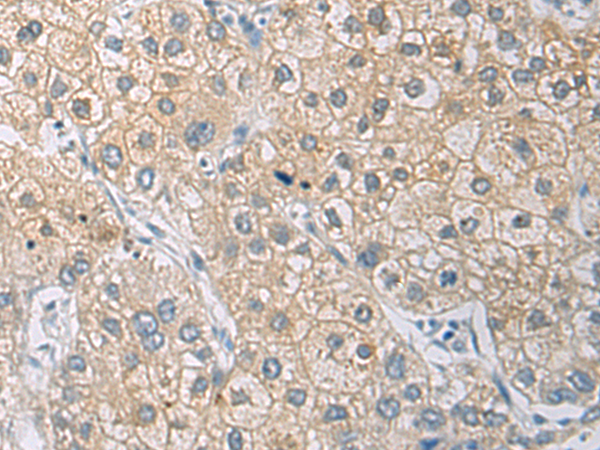

分类: 科研抗体货号: P12761别名: DIRA; IRAP; IL1F3; IL1RA; MVCD4; IL-1RN; IL-1ra; IL-1ra3; ICIL-1RA应用: IHC反应种属: Human